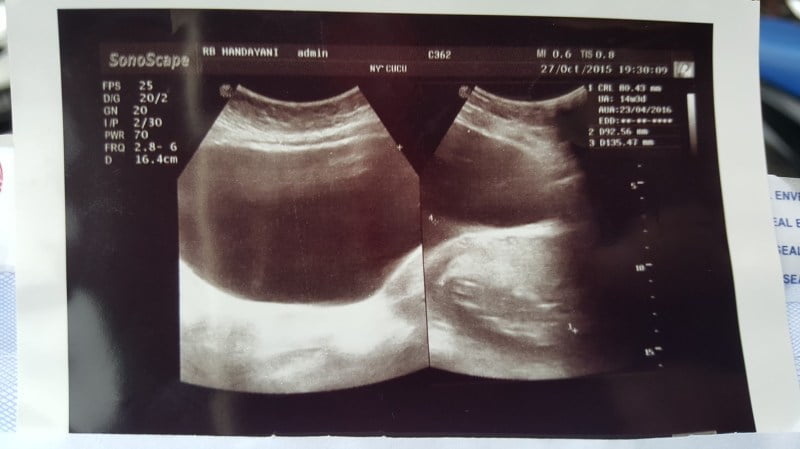

Masih tergolong jinak, isi kista ini berbentuk cairan. Jika dilihat dengan USG, bentuknya sangat mirip dengan kista fungsional. Namun bedanya, jika kista fungsional hilang dengan sendirinya setelah beberapa siklus menstruasi, maka cystadenoma akan terus membesar. Kista adenoma berukuran bervariasi dari 1-3 sentimeter hingga 30 sentimeter.

Dokter Anda mungkin secara berkala melakukan USG untuk memantau dan menentukan ukuran kista atau kondisi lain yang mungkin menimbulkan masalah. Dalam beberapa kasus, MRI (

) dapat dilakukan bila jenis dan bahaya kista tidak dapat ditentukan dengan USG. Jika kista membesar, ia berpindah (

), pecah dan menimbulkan gejala, atau terdapat risiko tumbuhnya kanker, biasanya dokter menyarankan untuk melakukan operasi pengangkatan kista.